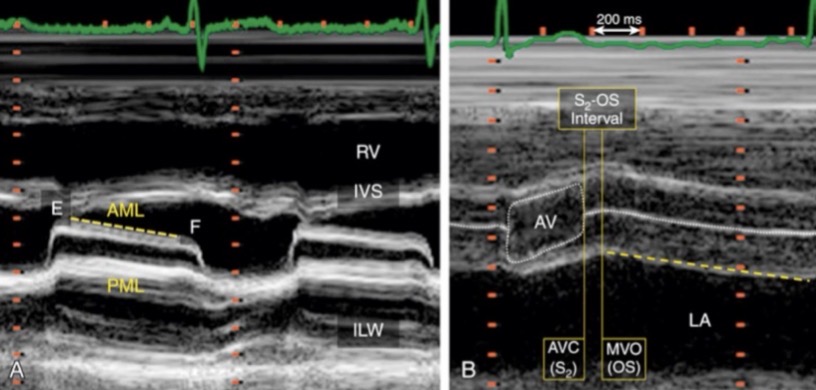

Below

In PSAX MR is seen ____ the anterior leaflet of the MV

Above

In PSAX AI is seen ____ the anterior leaflet of the MV

AI is above and MR is below

Which is MR and which is AI